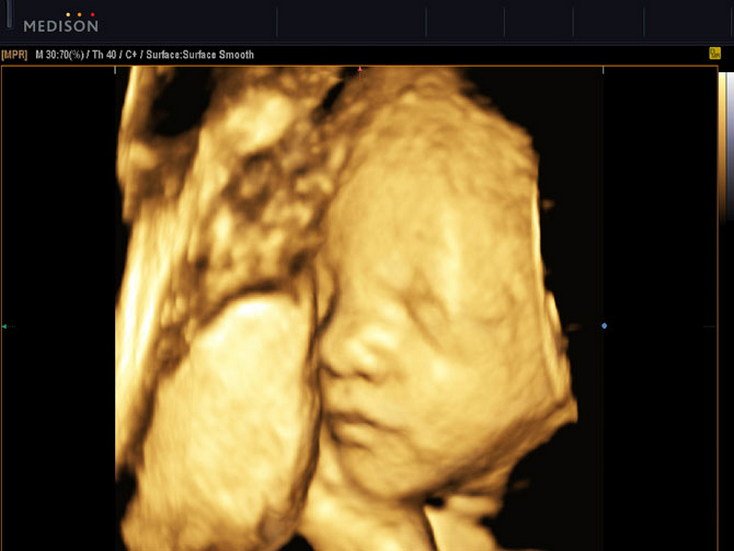

4D Foetal Face